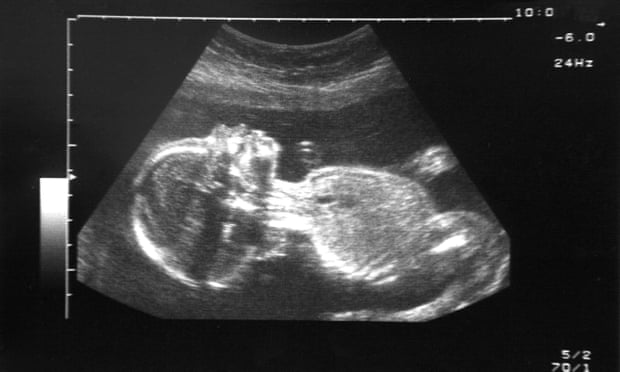

Recently, Dr. Tim Nawrot (from Hasselt University, Belgium), a health and environment specialist, showed the presence of black carbon particles in human placenta samples. It seems that these particles would enter the bloodstream through the capillaries of the lungs, and from there they would reach the placenta.

Optical microscopy (pulsatile laser post-illumination) image of a placental biopsy showing the presence of black carbon particles, denoted […]